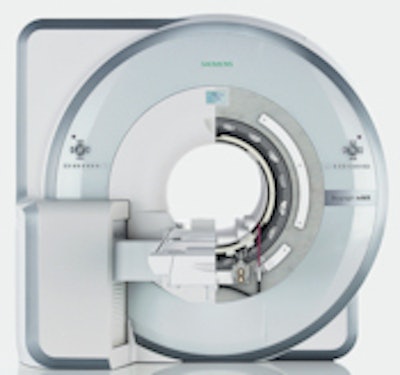

Multimodality vendor Siemens Healthcare of Malvern, PA, plans to take the next step into hybrid imaging with the launch of Biograph mMR, a new integrated PET/MRI scanner, later this month at the RSNA meeting in Chicago.

The work-in-progress scanner is a fully integrated, whole-body PET/MR system that features simultaneous data acquisition technology and a specially developed and designed PET detector array with lutetium oxyorthosilicate (LSO) crystals that fits inside the MRI.

| Biograph mMR PET/MRI. Image courtesy of Siemens Healthcare. |

"With normal detector technology, you cannot get a signal. So, therefore, it was necessary to develop a completely new, state-of-the-art PET detector technology with completely new cooling," said Britta Fuenfstueck, Siemens' CEO for molecular imaging. The PET detector "is integrated into the MR in such a way that you can do isocentric scanning and you are looking into the same field-of-view at the same time with the MR and the PET."